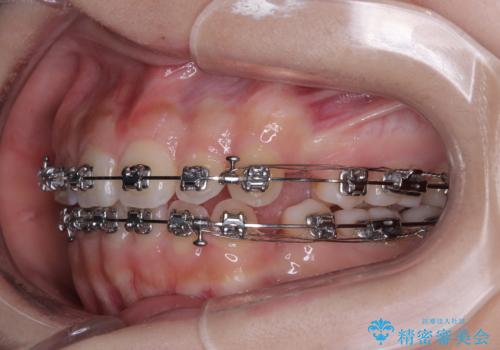

- 矯正装置

- メタルブラケット

- 2年2ヶ月

- 治療回数

- 10-30回